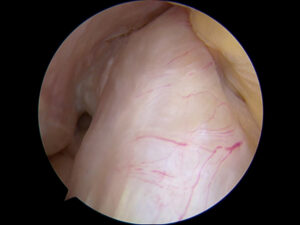

Arthroscopic image of a normal ACL.